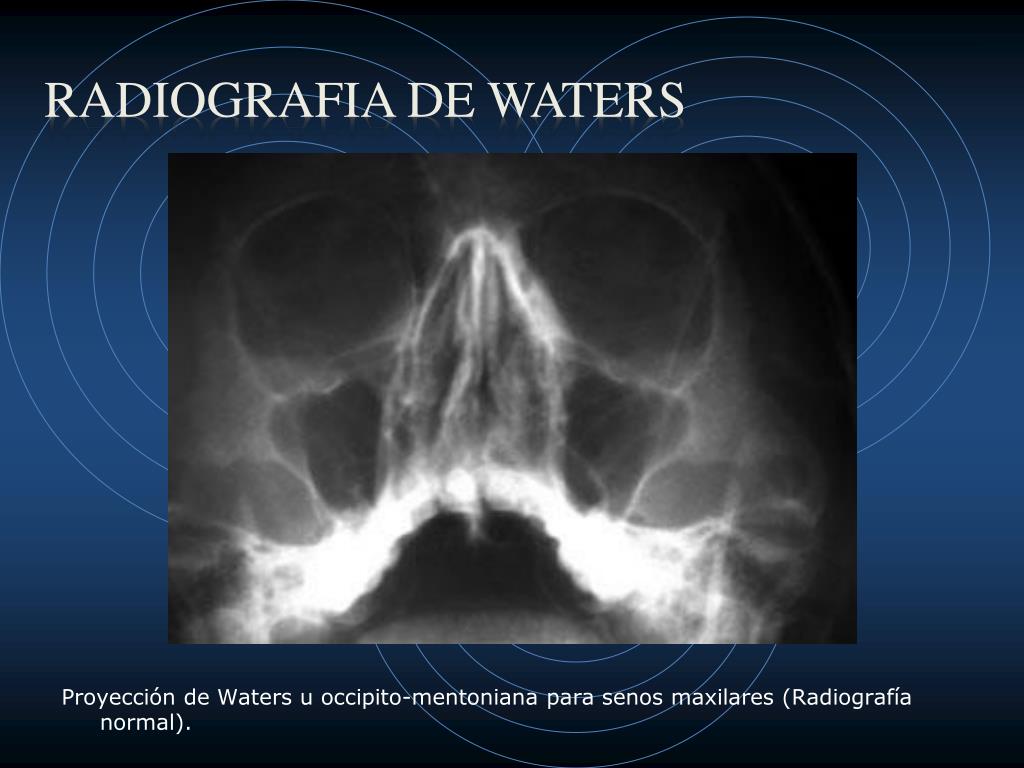

Download scientific diagram | Radiografía simple de cráneo en proyección de Waters, en la que se aprecia densidad aire en la órbita superior izquierda (Caso 2). from publication: Enfisema.

Radiología Tecnica de Waters - Descargar como PDF o ver en línea de forma gratuita. Proyeccion ap, lateral y oblicua del pie HillaryPerez7. Forma parte de serie radiográfica para evaluación de senos paranasales, junto a RX Caldwell y lateral de cráneo 4. La proyección de water es muy útil para estudiar el piso de la órbita,.

El estudio de "Rx Senos Paranasales 3 Proyecciones (Waters, Caldwell y Lateral)" implica la captura de imágenes radiográficas de los senos paranasales desde tres direcciones diferentes utilizando las técnicas de Waters, Caldwell y lateral. 1. **Técnica Waters**: En esta proyección, el paciente se coloca de pie o sentado con la cabeza.

Estudio de la identificación de las distintas estructuras que podemos describir en una Rx de cráneo (water)

El estudio de "Rx Senos Paranasales 1 Proyección (Waters, Caldwell o Lateral)" implica la toma de una radiografía de los senos paranasales desde una sola dirección utilizando una de las siguientes técnicas: Waters, Caldwell o lateral. 1. **Técnica Waters**: En esta proyección, el paciente se coloca de pie o sentado con la cabeza.

La opción ideal en la sospecha de cualquier traumatismo craneofacial es la TC. En caso de no disponer de tomografía, las proyecciones de radiología convencional más apropiadas en estas situaciones son: el Waters (occipitomental), la proyección de Caldwell (occipitofrontal), la lateral y la proyección de Hirtz o de arcos cigomáticos.